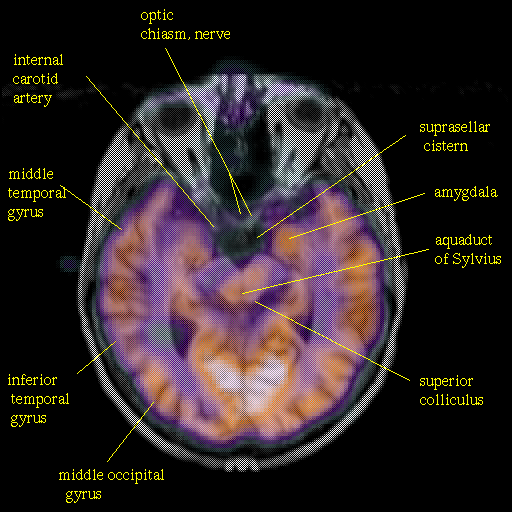

overlay: Slice 23

Slice 23

Pointers

Labeled